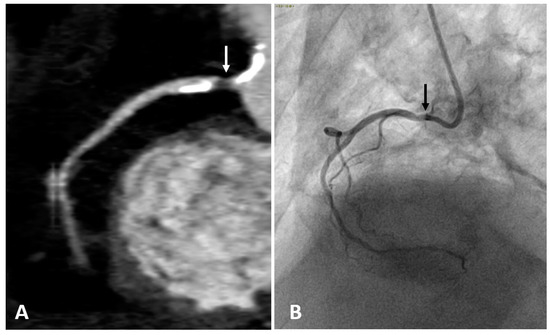

The intravenous administration of iodine contrast media allows the assessment of coronary stenosis and several adverse coronary plaque characteristics, such as spotty calcification, positive remodeling, and low-attenuation non-calcified plaques which identify a large necrotic core [68,69]. (Figure 2 and Figure 3). However, smaller components such as microcalcifications and TCFA cannot be detected because their dimension is ten times lower than the spatial resolution of CTCA (about 500 microns) [70].

Figure 2.

Right coronary artery (RCA) studied with CTCA (A) and with coronary angiography (B) in the same patient. Both examinations show a narrowing of the arterial lumen in the proximal RCA segment (arrows), indicating the presence of an atherosclerotic plaque. CTCA imaging shows a low-attenuation non-calcified plaque which identifies a lipid or necrotic core. Calcifications are hyperdense on CTCA, while not visible on coronary angiography.